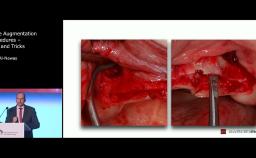

Surgical Planning and Procedures

WS2024 - When Immediate, Early or Delayed Placement in the Partially Dentate Patient

ITI World Symposium 2024 lecture by Daniel Buser - part of the "Immediacy" session.